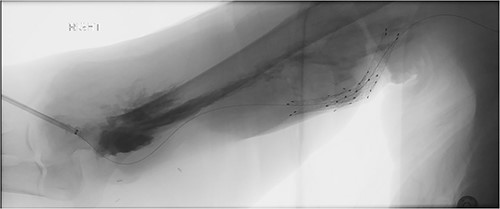

She then re-presented 2 months later with gradually increasing right upper extremity edema with a palpable thrill in the arteriovenous fistula. Duplex identified a large hematoma with patency of the fistula (Fig. 2). A tunneled dialysis catheter was placed to allow the swelling and hematoma to resolve. After medical optimization, the patient consented for operative intervention with the intention to evacuate the hematoma. There was noted to instead be a 20 × 35 cm PSA of the brachial artery (Fig. 3). The median nerve was identified and preserved. After proximal and distal control, the patient was heparinized, and the brachial artery PSA was decompressed with evacuation of large mural thrombi (Fig. 4). This artery segment was resected, and patch angioplasty was performed (Fig. 5). The fistula was ligated, and the distal remnant was preserved. Radial and ulnar pulses were palpable. The patient recovered well postoperatively.